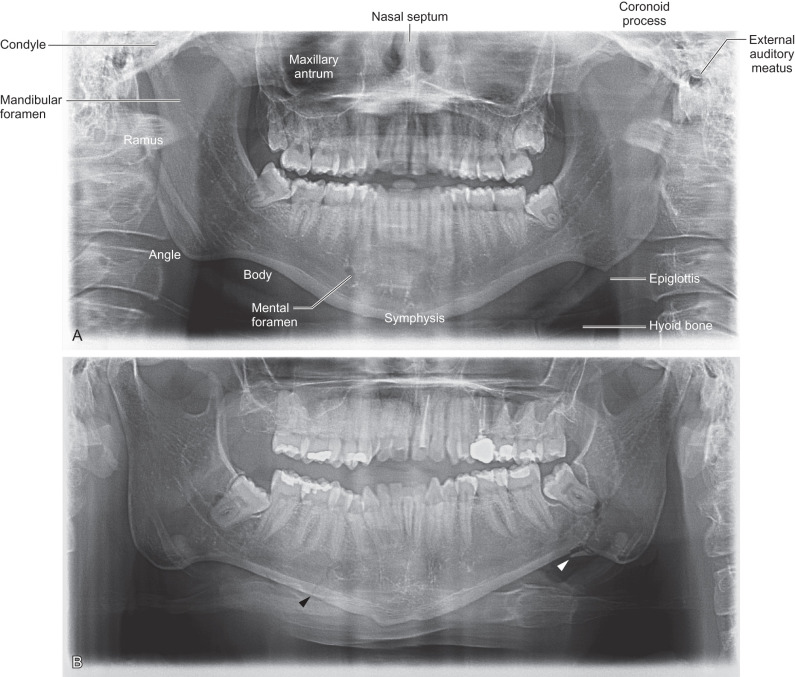

The panoramic radiograph (orthopantomogram or panorex) displays the entire maxillomandibular region on a single image ( Fig. 1.2.2A ). The term panoramic radiography is derived from panorama, “an unobstructed view of a region in every direction.” There are two different ways of obtaining panoramic views, which are defined by the location of the radiation source: intraoral or extraoral.

The intraoral technique requires a small X-ray tube be placed in the patient’s mouth where radiation is directed through the jaws to expose a film placed just outside of the targeted facial anatomy. The first patient undergoing this procedure was reported by a German inventor, Horst Berger. The extraoral technique, which is the most popular method in use today, employs an extraoral source of radiation that rotates around the patient. To create a panoramic view, objects in front or behind the focal trough are blurred, leaving a sharp image of the entire mandible in one 2-dimensional plane facilitating the diagnosis of mandible fractures and dentoalveolar trauma ( Fig. 1.2.2B ).

Panoramic radiographs are fast and convenient with minimal training needed for the operating technician. Moreover, panoramic radiography provides the lowest radiation dose with broad coverage of maxillomandibular bones and teeth. This imaging modality is most advantageous for stable patients who cannot tolerate intraoral procedures or examination. The limitations of the radiographs include unequal magnification across the image, making linear measurements unreliable, as well as difficulty imaging both sides of the mandible when the patient has severe maxillomandibular discrepancies causing malocclusion. The tomographic technique of the exam also creates artifacts, including double images of the hyoid bone, cervical spine, and epiglottis. Ghost artifacts, which are higher than the true anatomic location on the opposite side of the image, are created by the upward inclination of the X-ray beam. These artifacts, in addition to the superimposition of overlying structures, limit the complete evaluation of the maxillomandibular structures, especially the mandibular condyle and coronoid process which overlap the mastoid prominence and midface, respectively.